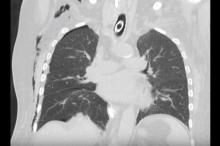

A 60-year-old patient was referred to the author’s clinic for operative treatment of diaphragm eventration with an unknown cause. Two months prior, the patient had been treated at another hospital for arterial embolism of the right leg, which was subsequently amputated. She was unable to be extubated, without obvious reason. Correction of the right hemidiaphragm was noted as a possible solution, with the goal of improving oxygenation and sink retention. The author performed a double-lined diaphragm plication by means of uniportal VATS with CO2 insufflation and use of the GelPOINT (Applied Medical, Rancho Santa Margarita, USA).

Despite some time-consuming adhesiolysis and the need for lung suturing at the end of the operation, incision to closure time was 120 minutes. Oxygenation remarkably improved after the operation, yet the comatose condition remained. The patient was referred back to the hospital where she initially had begun her therapy for further recovery.